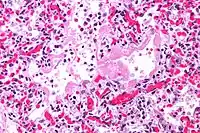

Патогенез ідіопатичного фіброзуючого альвеоліту натепер описується наступною схемою: спочатку ймовірний етіологічний фактор, досі не встановлений, пошкоджує структурний прошарок, який розділяє порожнину альвеоли та просвіт капіляру. Унаслідок цього розвивається інтерстиційний та внутрішньоальвеолярний набряк, що запускає механізм репаративних процесів у пошкоджених тканинах. Це призводить до проникнення до інтерстиційної тканини та стінок альвеол клітинних елементів крові — лімфоцитів, моноцитів, плазматичних клітин, еозинофілів; а також проникнення епітеліально-клітинних медіаторів запалення і факторів зсідання крові. Усе це призводить до дезорганізації структурної основи альвеол, зміни кількісного та якісного складу сурфактанту, наслідком чого є колабування альвеол та порушення аерогематичного бар'єру; а ураження ендотеліальних клітин призводить до порушення захисної функції альвеол, порушення метаболізму та трофіки легеневої тканини, а також до порушення динамічної рівноваги брадикініну—ангіотензину. Продовження репаративних процесів у пошкоджених ділянках призводить до надмірного синтезу колагену, що сприяє формування фіброзу легеневої тканини. Надмірне руйнування нейтрофілів, які інфільтрують легеневу тканину у хворих на ідіопатичний фіброзуючий альвеоліт, спричинює надмірну активацію протеолітичних ферментів, що призводить до запуску синтезу патологічного колагену. Активують синтез колагену альвеолярними макрофагами також лімфокіни, які виробляються лімфоцитами, які в свою чергу також сприяють проліферації фібробластів.[17][5] У подальшому при розвитку симптомів ідіопатичного фіброзуючого альвеоліту від альвеолярного та інтерстиційного набряку через стадію альвеоліту до інтерстиційного фіброзу формується так звана «стільникова легеня», яка й вважається кінцевим підсумком та основним патологоанатомічним субстратом даного захворювання.[18]